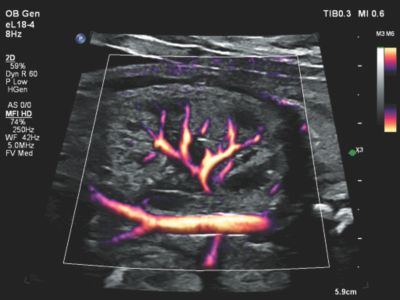

Flow Viewer applied to MFI HD with eL18-4 fetal kidney

Performance you can see with Microflow Imaging HD

MicroFlow Imaging (MFI HD/MFI) is designed to detect low-volume, low-velocity blood flow found in fetal, placental, uterine and ovarian vasculature. MFI overcomes many of the technical barriers associated with conventional methods to detect small vessel blood flow with high resolution and minimal artifacts.

MFI also maintains high frame rate and 2D image quality while applying artifact reduction techniques. 2D image subtraction, 2D blending and side-by-side display options offer excellent visualization versatility.